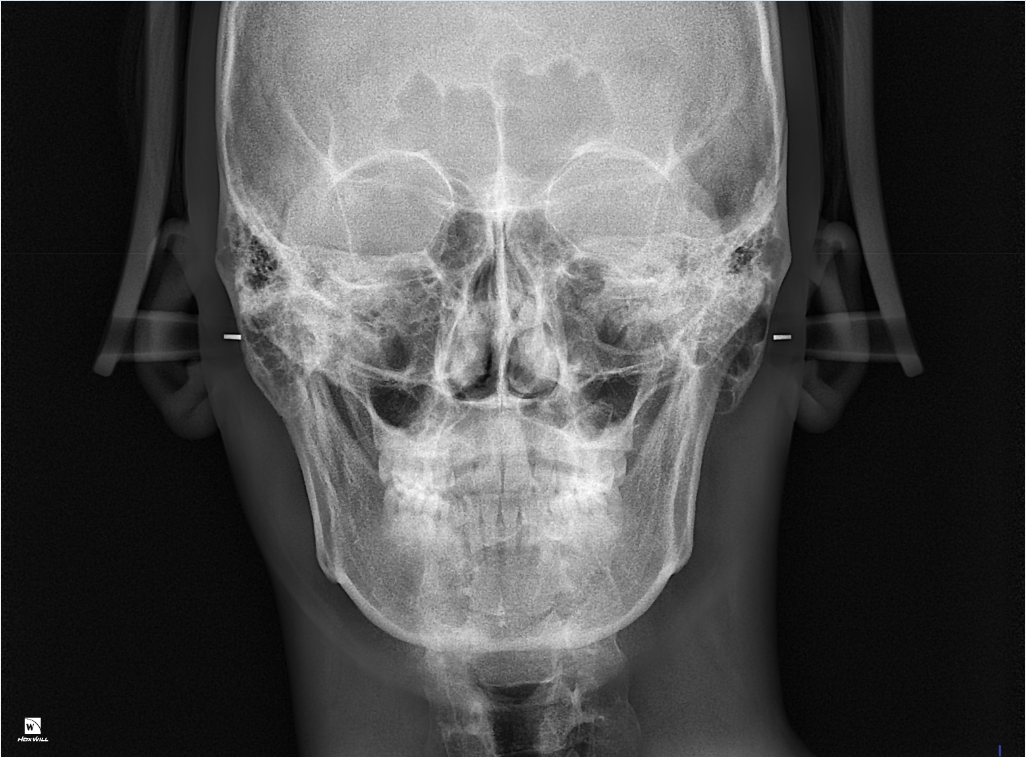

턱이 왼쪽으로 canting 되어있어도 어금니 교합이 맞을수 있나요?

턱이 왼쪽으로 비대칭이 약간 있는데 그래도 어금니 교합이 맞을수있나요?

• 2번 째 사진

일전에도 문의주신 것으로 기억합니다. 현재 좌측으로 canting 되어 있으나 이는 사람에 따라서는 치료의 대상이 아닐 수도 있습니다. 모든 사람은 양쪽으로 모두 대칭인 수평인 경우는 거의 없으며 한쪽으로 canting되어 있는 경우가 많습니다. 이때 canting 범위에 따라 정상일 수도 있고 정상이 아닐 수도 있으나 이는 본인이 심미적으로 전혀 문제가 되지 않는다고 본다면 치료를 하지 않아도 됩니다.